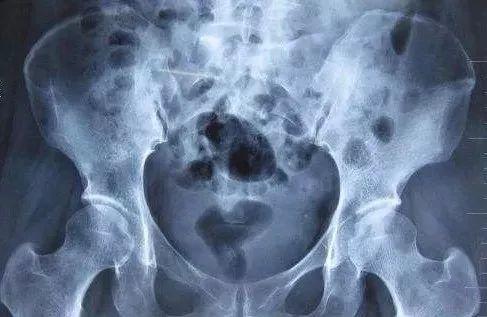

由于姐姐和女儿都在广州工作生活,一家人拿到胸部CT结果就赶紧商量,最后决定来广州治疗,行动力极强的刘叔当天下午就坐飞机到达了广州。对暨南大学附属复大肿瘤医院早有耳闻的刘叔一家找到了王远东院长,王院长凭着40多年临床经验,看了刘叔在温州拍的CT就觉得问题严重,但单凭一张片子还不能完全确定,建议刘叔马上做全身PET-CT,结果显示全身骨质疏松,全身骨骼广泛穿凿样、虫蚀样溶骨性骨质破坏,部分伴软组织形成,代谢增高。免疫蛋白电泳呈阳性,骨髓穿刺活检提示骨髓瘤细胞占34%,经过一个多月,刘叔终于找到“真相”,被诊断为多发性骨髓瘤。 刘叔在9月初进行骨髓穿刺活检,提示骨髓瘤细胞占34%